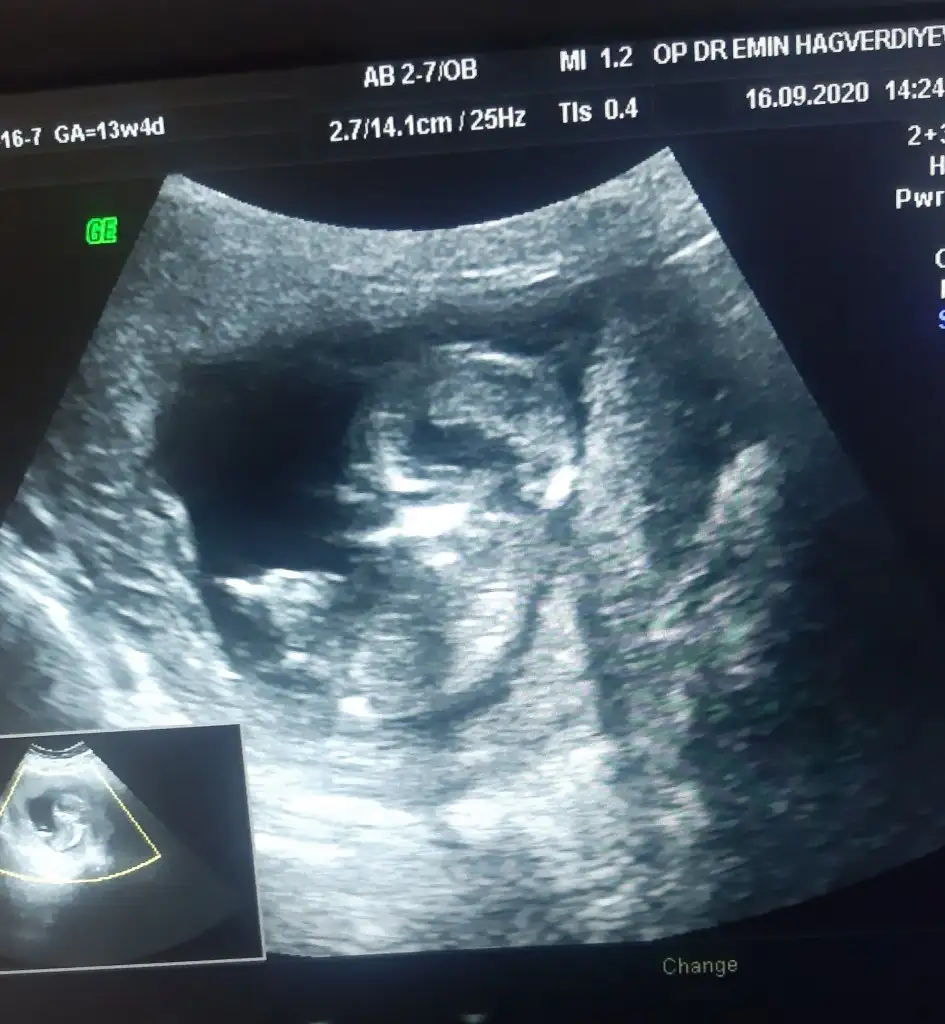

Yine hic net degil doktor.gordum dedi ama yorum mersk ediyorum doktor yuzdede vermedi netde demedi ama bilemedim belki bisiyler dersin son kez cnm bikac kezde atmıştım doktor yine ultrason goruntusu vermedi net goruntu yakalayamadi diye ben ekrani cektim Ikra meyra Ikra meyra 13+4

20200916_174747.jpg

Yine hic net degil doktor.gordum dedi ama yorum mersk ediyorum doktor yuzdede vermedi netde demedi ama bilemedim belki bisiyler dersin son kez cnm bikac kezde atmıştım doktor yine ultrason goruntusu vermedi net goruntu yakalayamadi diye ben ekrani cektim Ikra meyra Ikra meyra 13+4Eki Görüntüle 2691630

Nub iyi gozukmoyor ama sanki erkek